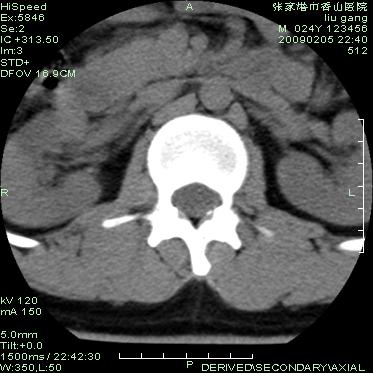

以下是引用随光逐影在2009-3-11 14:43:00的发言:[br]平片:l3、4、5及s1前上缘见类似“切角征”。[br]ct扫描:腰椎多个节段椎间盘向椎体内(椎体前部)突出。